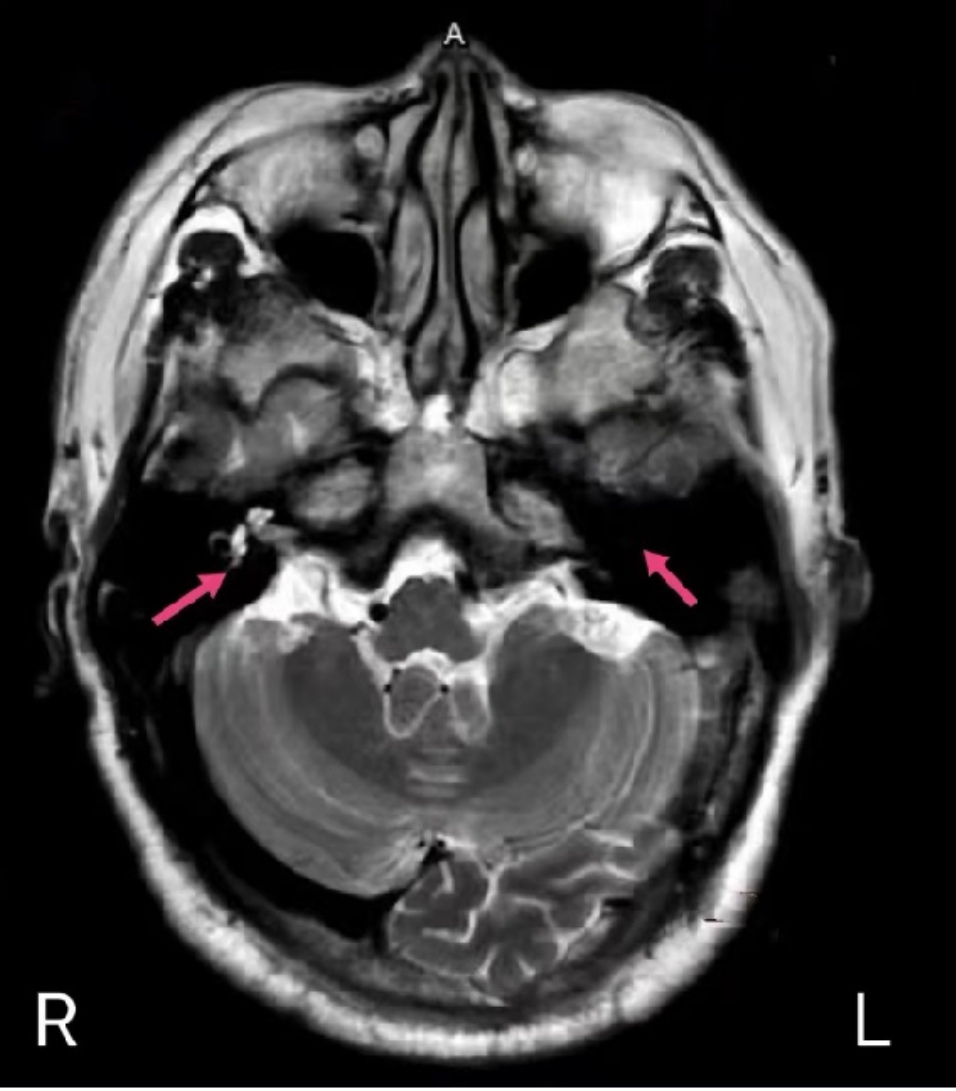

令医生疑惑的是,经对比以往就医的影像检查结果,刘叔左耳的前庭、耳蜗、半规管等内耳结构,竟然消失了!

磁共振显示左耳内耳结构消失,红色箭头所示

经中山一院人工耳蜗植入团队多学科会诊评估,由于耳蜗结构消失,刘叔的左耳已不合适人工耳蜗植入。同时,考虑到脑膜炎后容易出现右耳耳蜗骨化,为挽救刘叔的听力,专家建议尽快做右耳人工耳蜗植入。